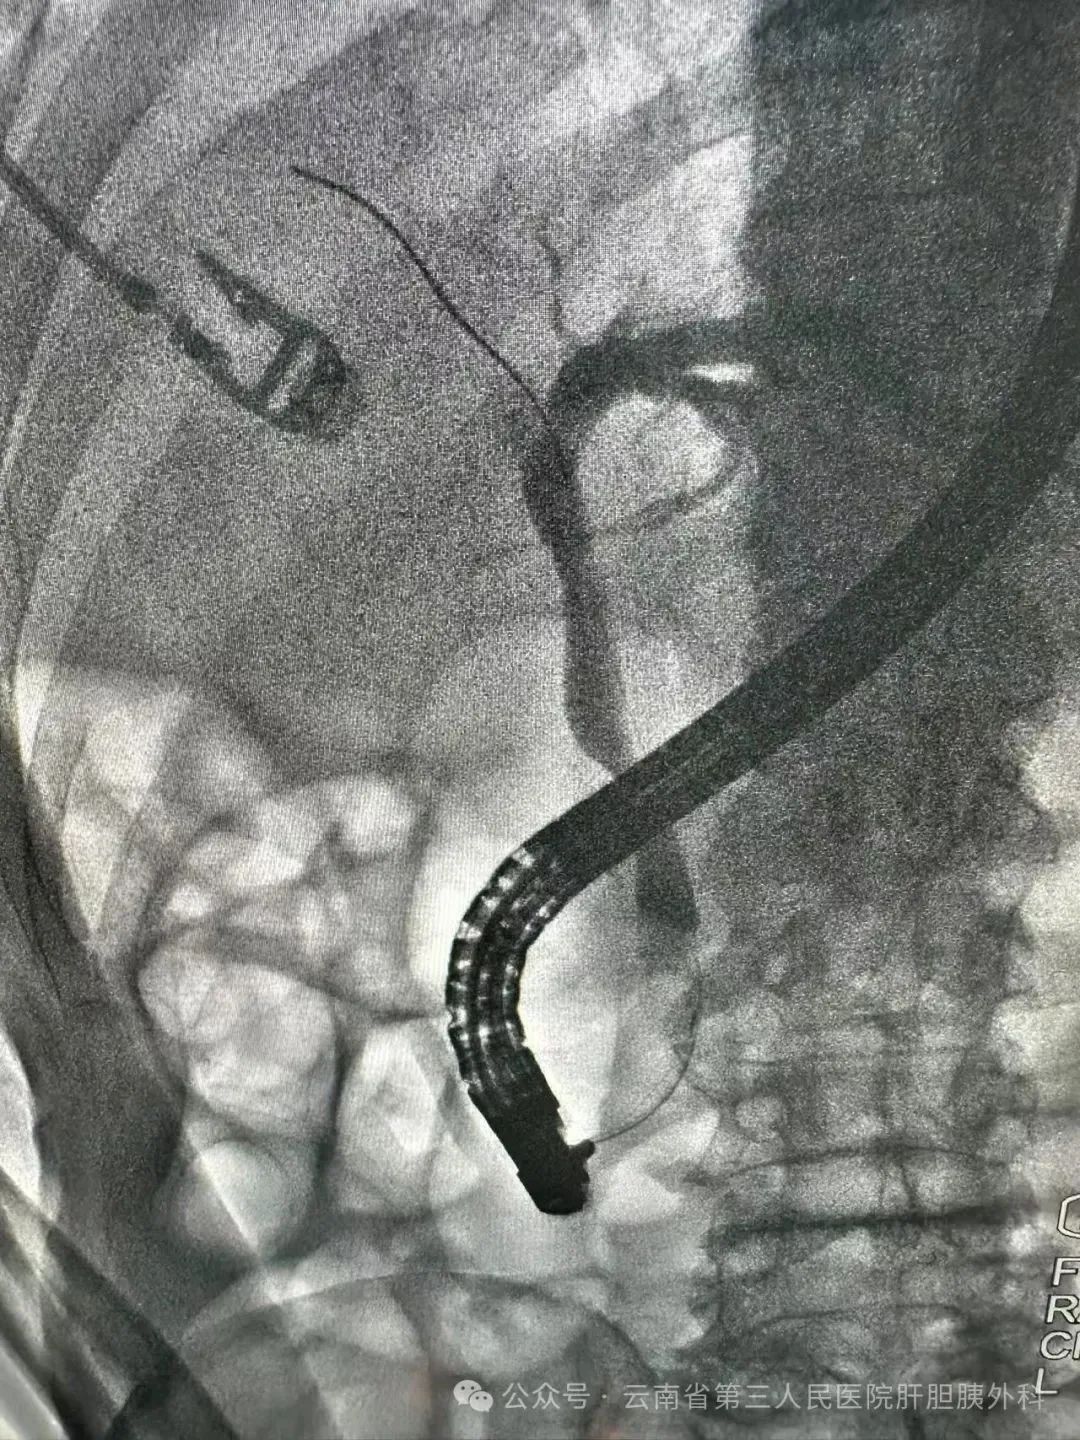

近日,云南省第三人民医院肝胆胰外科为一位百岁高龄,因胆管结石合并急性化脓性胆管炎的患者实施急诊ERCP手术,成功挽救了患者生命。

经过紧急会诊和全面评估,肝胆胰外科内镜团队决定立即为患者实施急诊ERCP手术。患者虚弱的身体状况和胆道系统的高度梗阻使得内镜微创手术的难度陡增,狭窄的胆管增加了插管的困难,患者的心肺功能衰退更使术中不良事件的发生风险倍增。

最终,手术团队凭借丰富的经验和精湛的技术,准确迅速地完成了插管,顺利将胆管结石取出,同时引流出大量脓性胆汁,成功解除胆道梗阻,挽救了患者的生命。

术后通过留置鼻胆管持续引流,患者感染症状迅速缓解,黄疸消退,生命体征逐渐平稳。